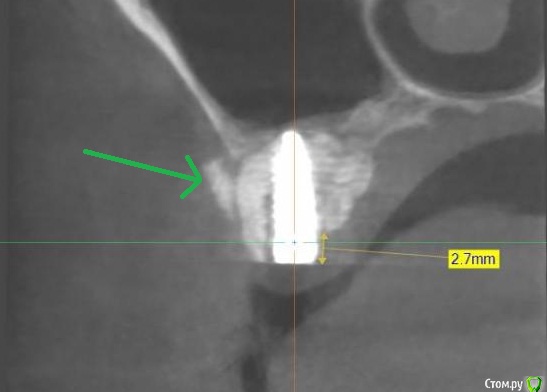

Norton Опубликовано 14 апреля, 2019 Поделиться Опубликовано 14 апреля, 2019 (изменено) Доброго времени суток уважаемые коллеги. Ко мне обратилась пациентка с установленным импл. в области верхней 6 (XIVE 3.8 / 11 мм). Сейчас назревает вопрос нужна ли мягкотканная пластика или нет? Cмутило то, что несколько коллег в моем городе порекомендовали сделать. Изменено 14 апреля, 2019 пользователем Norton Ссылка на комментарий

Дмитрий М Опубликовано 18 апреля, 2019 Поделиться Опубликовано 18 апреля, 2019 (изменено) отлом вестибулярной или миграция графта?похоже свободный фрагмент, пальпируется нет? Изменено 18 апреля, 2019 пользователем Дмитрий М Ссылка на комментарий

Magadalina Опубликовано 19 апреля, 2019 Поделиться Опубликовано 19 апреля, 2019 Похоже на выход графта сразу после синус- лифтинга через окно. Это никакого значения не имеет Ссылка на комментарий

Norton Опубликовано 20 апреля, 2019 Автор Поделиться Опубликовано 20 апреля, 2019 что это.jpg отлом вестибулярной или миграция графта?похоже свободный фрагмент, пальпируется нет?Нет, я на это тоже обратил внимание Ссылка на комментарий